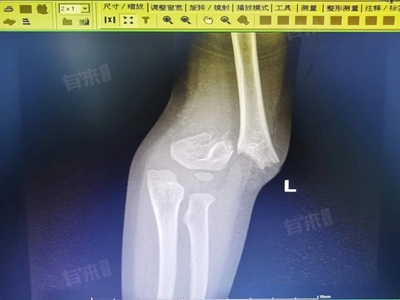

- 但若患者发生严重骨折,包括移位骨折、粉碎性骨折,或骨折压迫重要内脏器官、椎管、神经等。此类骨折如果不进行复位固定和后期功能锻炼,可能导致严重后果,如出血、器官功能障碍等,需要积极治疗干预。

对于骨折错位比较明显的患者,由于骨折断端明显分离,无法自行长好 ,需要进行手术治疗,恢复骨折断端的对位对线,促进骨折稳定和愈合。在发生骨折后,应及时就医,根据医生的诊断和建议进行治疗。同时,骨折愈合是复杂的过程,需要患者与医生密切合作,遵循适当康复计划,促进骨折愈合和恢复。